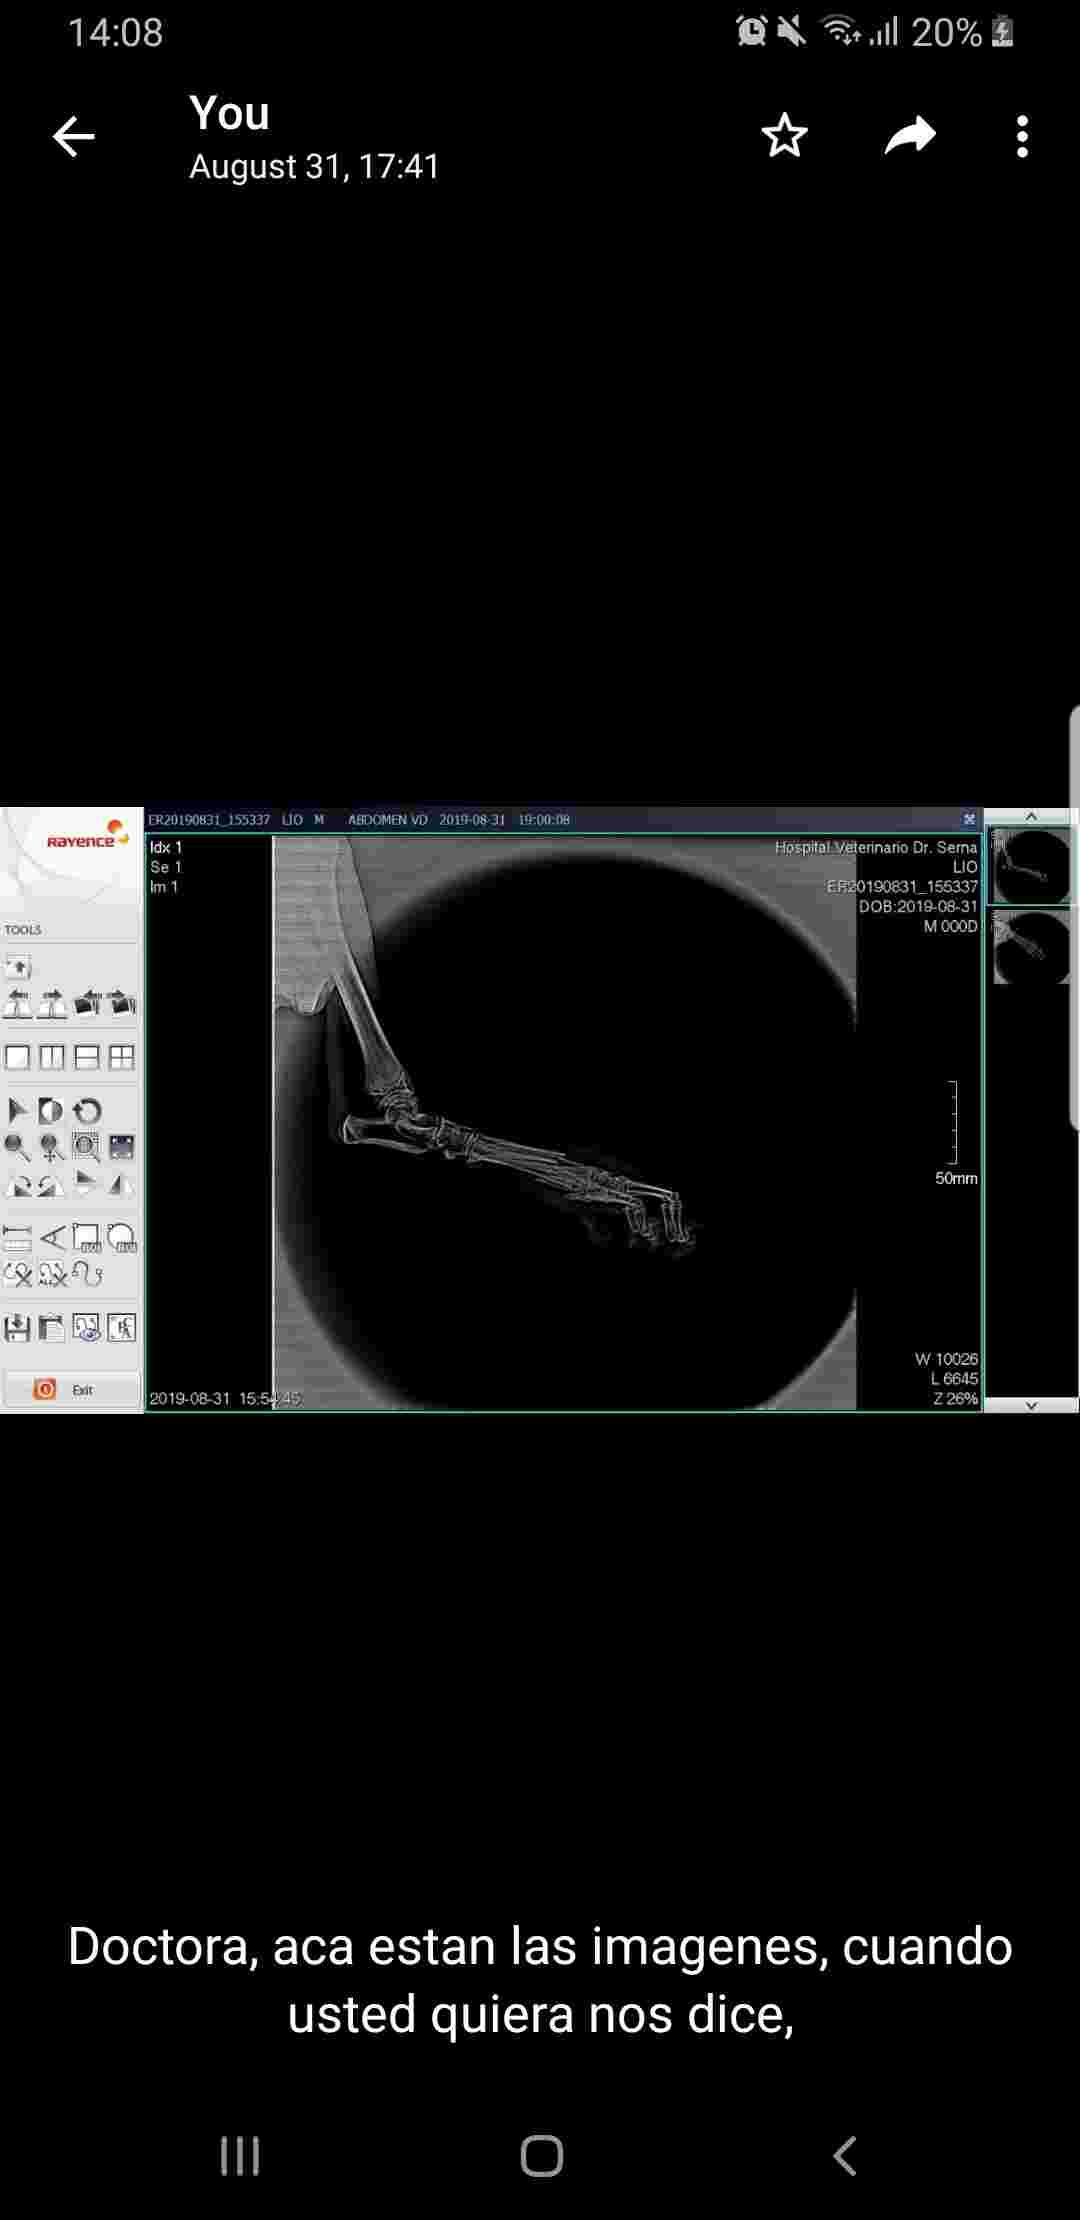

My dog was bitten in the leg/paw by my other dog. Should my dog get a cast or screws? Also when i touch his tail it hurts him, how can i know if its also fractured?

This question includes photos that may contain sensitive content. Click to view.

Hello, and thanks for your question on Petco Pet Education Center, formerly Petcoach. I have to defer your question about Leo specifically to the vet who is treating him and took the x-rays, since they will have access to all the information from his exam that I don't have, but I can tell you that in general I do not usually recommend casts or screws for broken toes. Most of the time broken toes heal very well with strict rest alone, especially in young patients. The "strict rest" is very important - I usually encourage owners to use a crate as much as possible until the bone forms a callous and stabilizes the fracture. The best way to evaluate for a tail fracture is with an additional x-ray, but again the tail is another area that usually heals well with rest and pain control. However, if the foot fracture was due to a bite wound, it is important to make sure that the pain isn't related to an infection, which would require oral antibiotics to treat. I hope this helps!